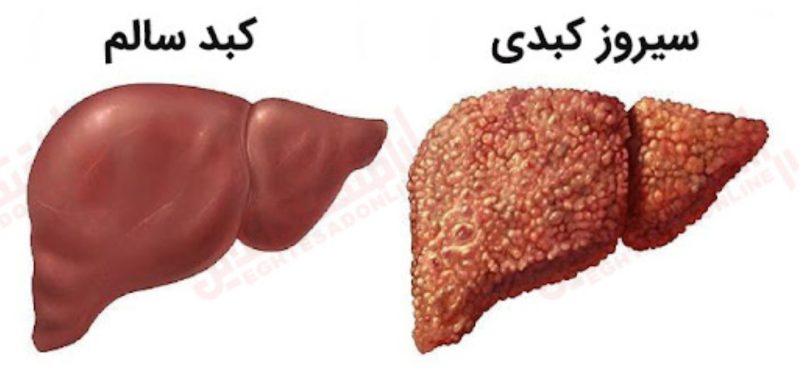

سیروز: تهاجمات مکرر ویروس ها، مواد سمی و دیگر عوامل بیماری زا به بافت های کبد آسیب می رساند و در نهایت جریان خون مطلوب در این اندام را مختل می کند که به آن «سیروز» یا «التهاب شدید کبدی» گفته می شود. عدم درمان درست و کامل در 20 تا 25 درصد موارد هپاتیت مزمن به سیروز کبدی می انجامد.